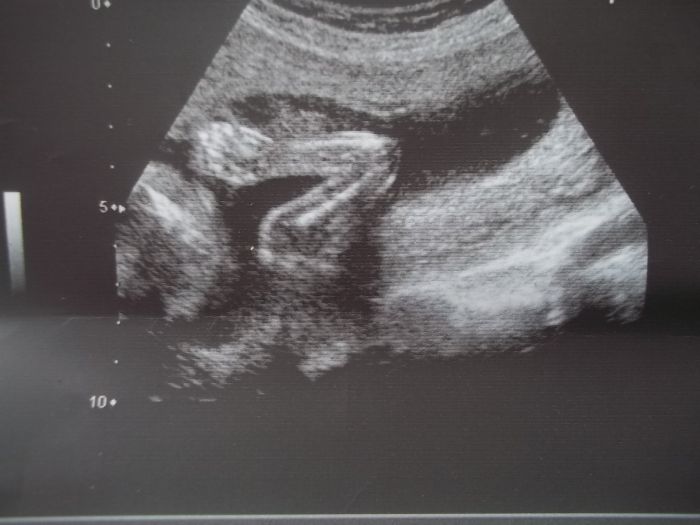

Dneska jsem se těšila, že konečně budu vědět pohlaví, ale miminko nám na ultrazvuku akorát zamávalo

a bylo stále zády, takže musíme vydržet až do 17.3. na velký ultrazvuk, jinak vše v pořádku